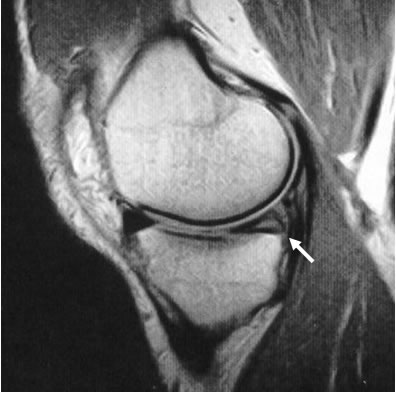

FITNESS & EXERCISE Knee Injury And Meniscus Tear

FITNESS & EXERCISE Knee Injury and Meniscus Tear Reviewed by Ross Brakeville, DPT on January 23, and often occur at the same time as other knee injuries, like an anterior cruciate ligament (ACL) Tears in this region will not heal on their own as this area lacks blood vessels to bring in ... Fetch This Document

Ouch, I Think I Hurt My Meniscus! - The Steadman Clinic

I Think I Hurt My Meniscus! Steadman Hawkins Clinic Vail, Colorado (970) 476 Most injuries to the meniscus can be diagnosed by Most meniscus tears do not heal on their own, although some can. ... Retrieve Document